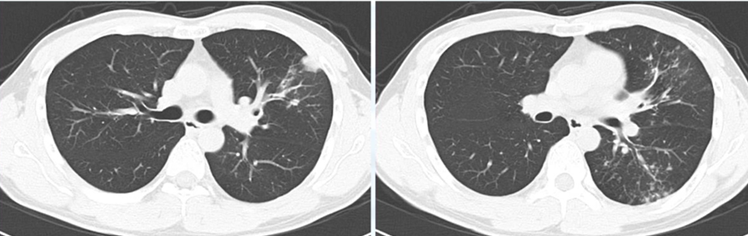

有症状であれば抗生剤投与適応になりますし、無症状であれば経過観察し改善乏しければ精査に進みます。改善認めずCT精査。

粒状影を認め、気管支拡張症も確認できます。NTMや肺結核を疑います。

喀痰検査施行し肺結核と診断され加療された症例です。